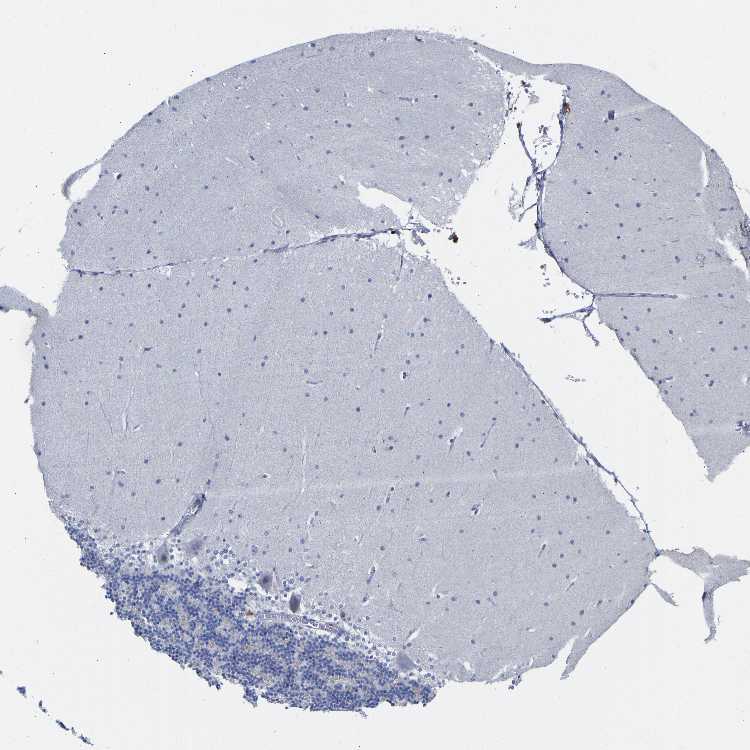

CEREBELLUM - Antibody stainingi

Antibody staining in the annotated cell types in the current human tissue is reported as not detected, low, medium, or high, based on conventional immunohistochemistry profiling in selected tissues. This score is based on the combination of the staining intensity and fraction of stained cells.

Each image is clickable and will lead to virtual microscopy that enables deeper exploration of all samples and also displays staining intensity scores, fraction scores and subcellular localization as well as patient and tissue information for each sample.

Antibody HPA018858Antibody CAB025943

Purkinje cells Not detectedNot detected

Cells in granular layer Not detectedNot detected

Cells in molecular layer Not detectedNot detected